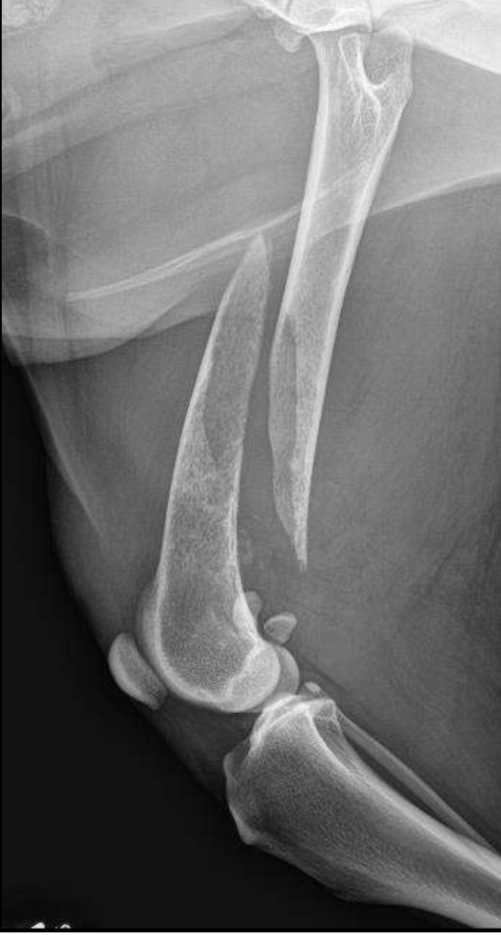

What is a spiculated periosteal reaction?

Periosteal reaction perpendicular to the cortex along the Sharpey’s fibers

What does spiculated periosteal reaction appear as?

Columns of bone or radiating like a sun burst

When is columnar spiculated periosteal reaction seean?

Diseases like hypertrophic osteopathy

What periosteal reaction

Palisading periosteal reaction

What periosteal reaction?

Sun burst